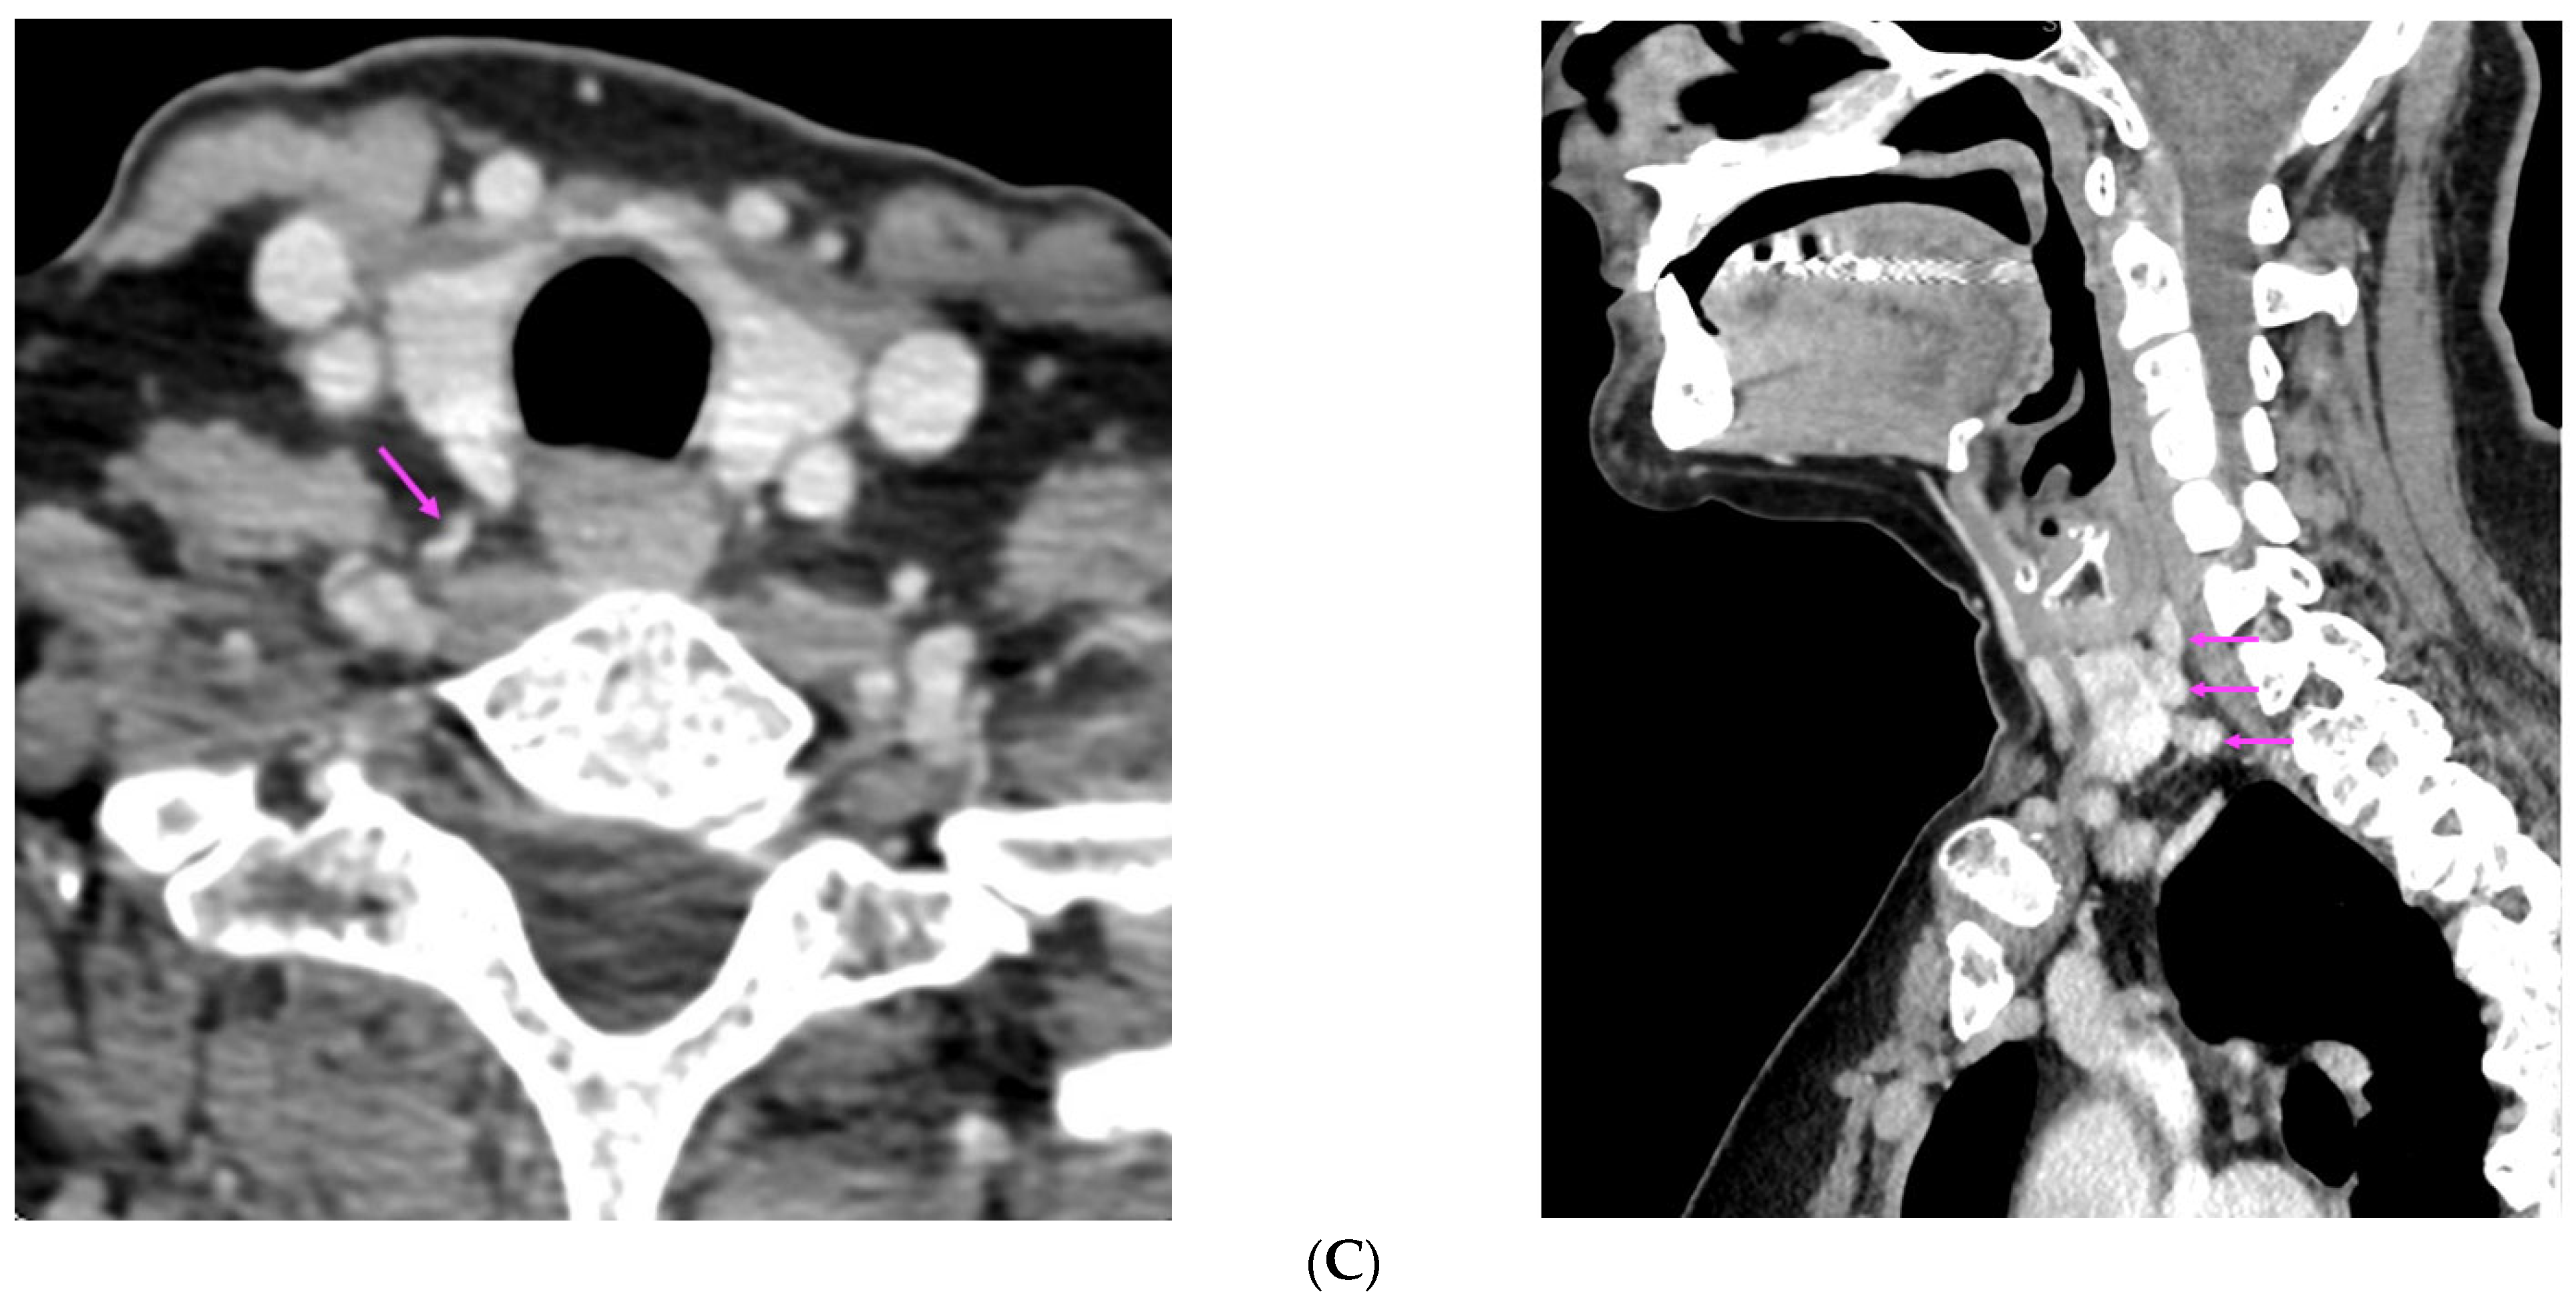

| [37] | US: six nodules of 5 mm to 16 mm located subcutaneously anterior of right sternocleidomastoid muscle 99m-Tc sestamibi scintigraphy: no hyper-functional foci CT: similar to US | Parathyromatosis |

| [38] | 99m-Tc-MIBI imaging (SPECT/CT): three foci of elevated uptake on early phase with slow washout on delayed phase | Hyperplastic parathyroid tissues |